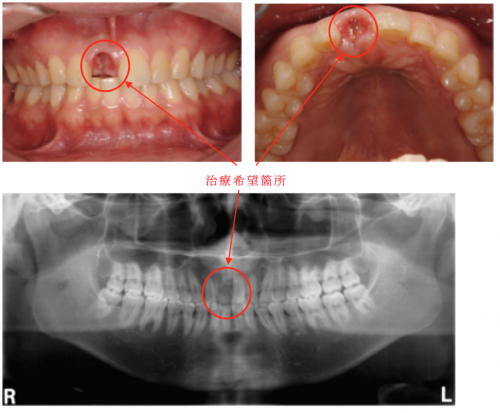

【注意事項】・本商品は裁断済みです。・スキャン目的のため、1ページずつバラバラの状態になっています。・裁断済みのためやや傷や汚れありのコンディションにしていますが、中のページにつきましては、書き込みや大きな汚れはなく、比較的良好な状態です。・裁断済みであることをご理解のうえ、ご購入をお願いいたします。・裁断済みを理由とした返品はご容赦ください。インプラントに関する専門的な知識を網羅した書籍。- タイトル: インプラントの咬合- 著者: 細山愃 他- 内容: インプラントに関する専門的な知識を提供する書籍- 出版社: クインテッセンス出版ご覧いただきありがとうございます。